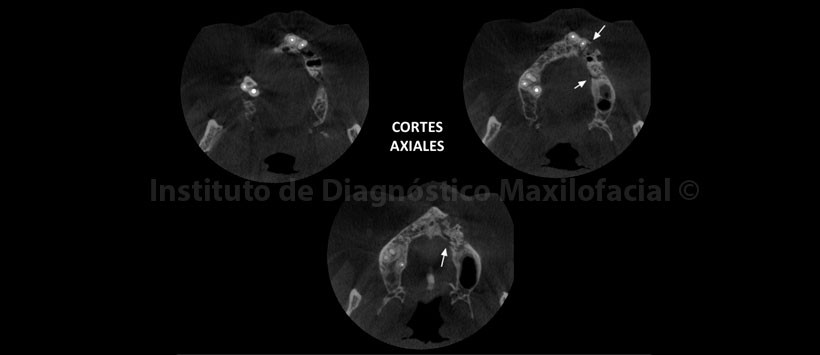

A la evaluación de la tomografía volumétrica (CBCT) en los cortes axiales (Figura 2, 3), coronales (Figura 4,5), transaxiales (Figura 6,7) y tangenciales (Figura 8), se aprecia proceso osteolítico de límites mal definidos, bordes difusos, localizado a nivel del maxilar superior del lado izquierdo, que se extiende en sentido mesio-distal desde la pieza 2.2 hacia los lechos alveolares de las piezas 2.3 y 2.4 y en sentido cefálico-caudal de la címa de reborde alveolar hasta el piso del seno maxilar a nivel de la zona de pieza 2.5. Se aprecia, presencia de secuestros óseos y reacción periostal en la tabla ósea vestibular y en zona del piso del seno maxilar.